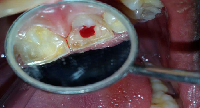

A 15 year old male patient came to the Department with the complaint of continuous dull pain on his upper left central incisor. He also gave a history of traumatic injury when he was eight years old for which he didn't undergo any dental treatment. He had noncontributory medical history. On extraoral examination, no abnormality was detected. Intraoral examination revealed there was no sign of caries, no crown discoloration, no swelling and no sinus tract was present. Gingival tissue and tooth were intact. On palpation, the patient felt mild pain on the root area of affected tooth. On percussion, dull percussion note was present.